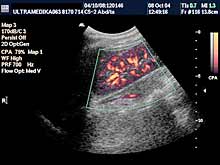

Posebni pregledi:

- Fokalne promene jetre, pankreasa i ostalih parenhimatoznih organa (3D

Sono CT procena i procena vaskularizacije sa Broad band-CD i PD i 3D

CPA modom).

- Broadband-CD i CPA pregled portne cirkulacije

- Broadband-CD celijačnog pleksusa

- Broadband-CD i CPA Aorte i ilijačnih arterija.